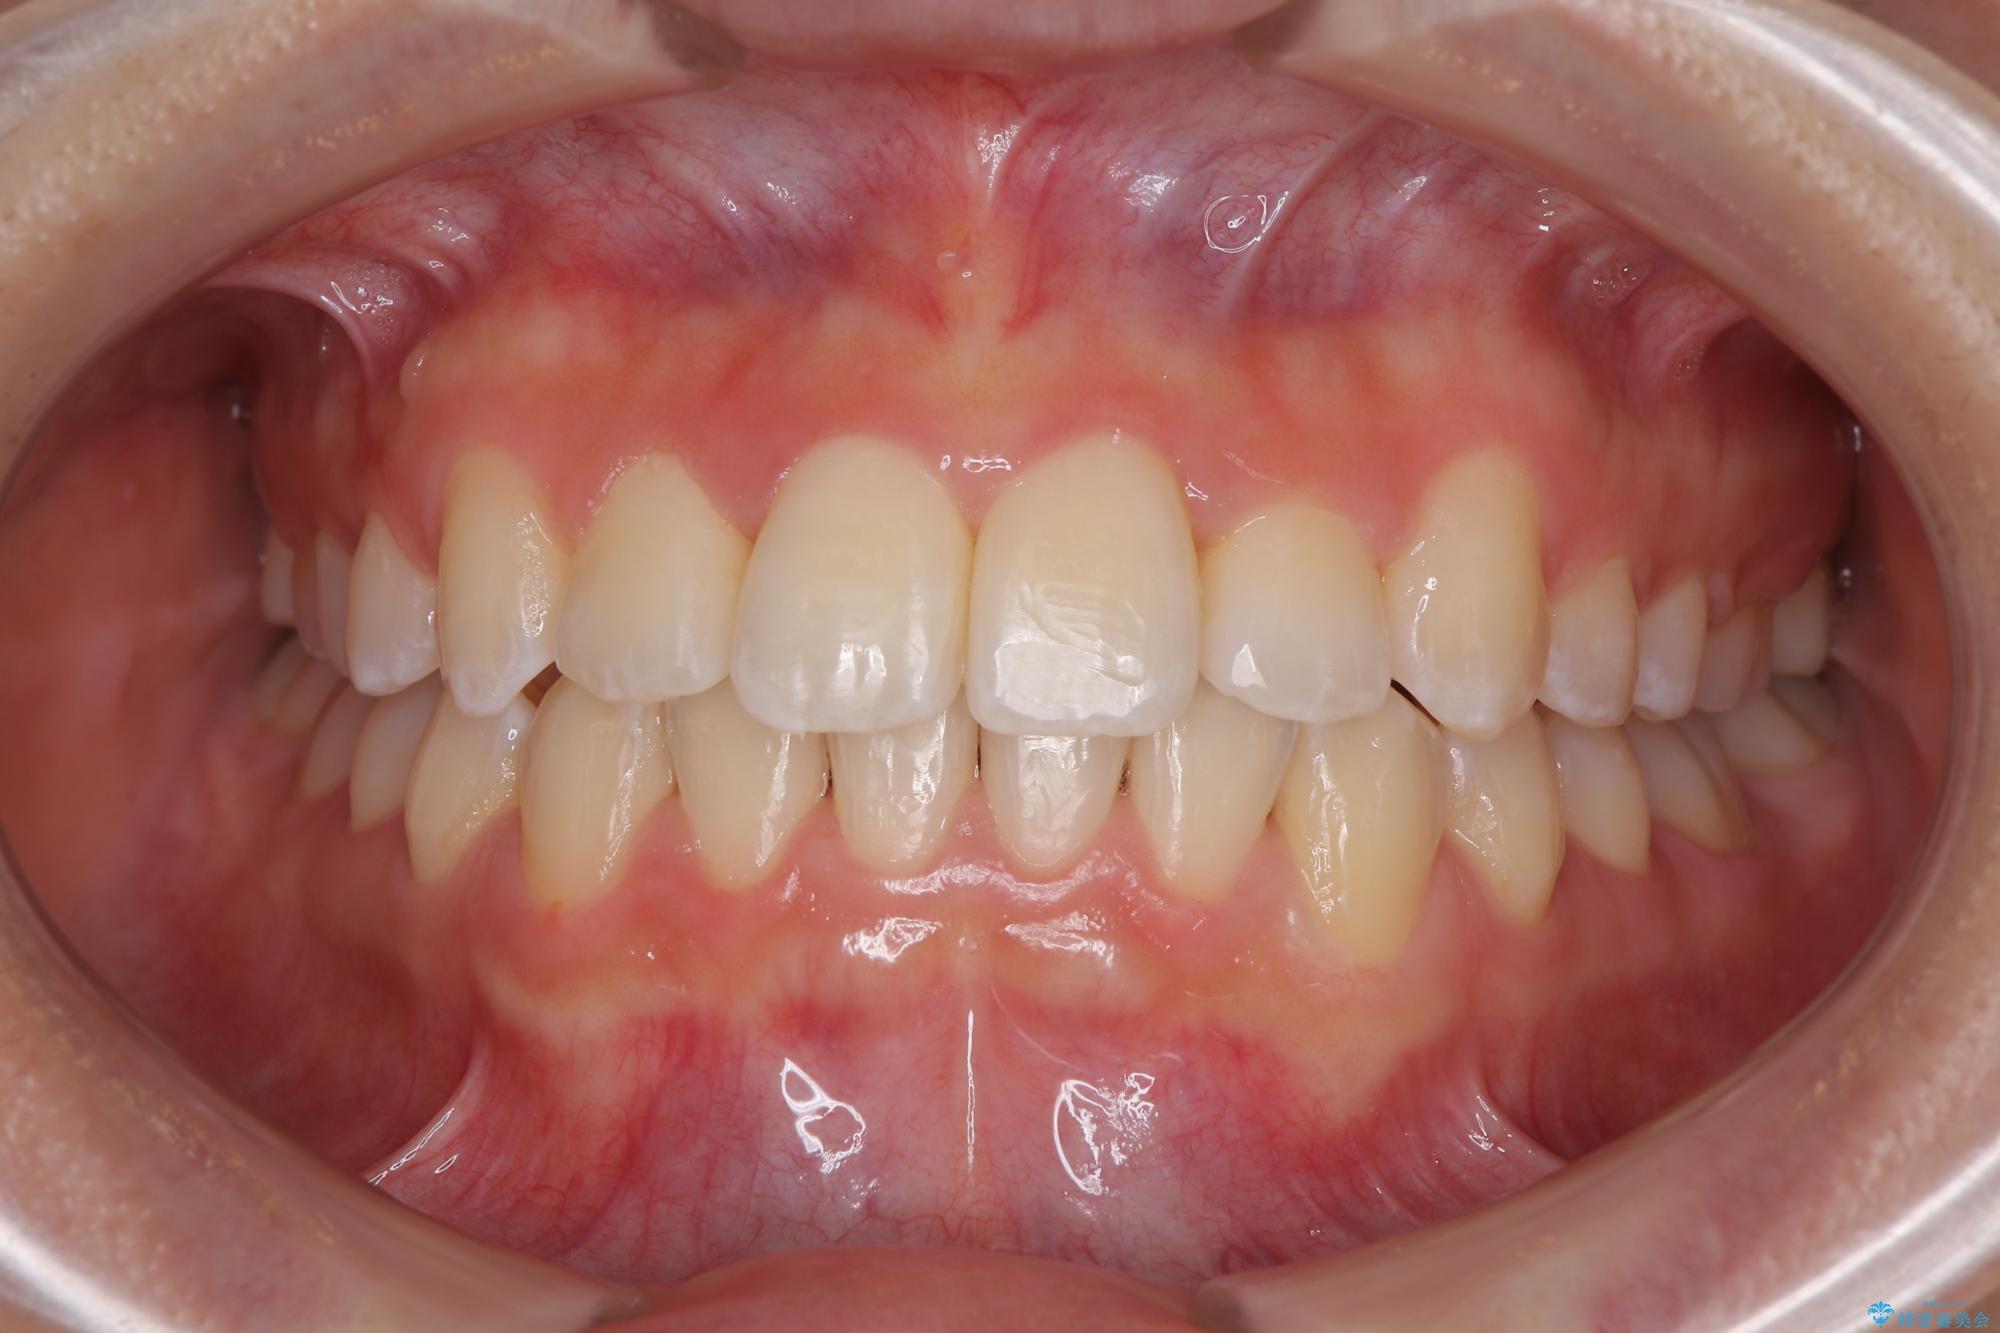

前歯のクロスバイト 裏側に隠れた歯をワイヤー装置で短期間治療

装置の外見を気にしていましたが、短期間で治療を終えることができるだろうと伝えると、安価であるメタルブラケットを選択されました。

想定通り、1年強で綺麗に仕上げることができました。